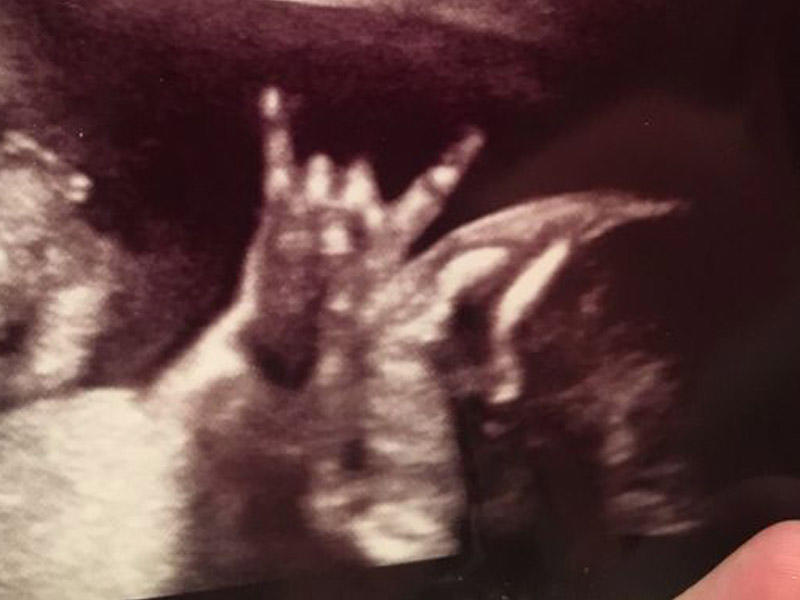

Jared və Makelle Ahlin adlı cütlük ultrasəs müayinəsinin görüntülərinə baxanda şoka düşüblər.

7News.az "Mirror"a istinadla bildirir ki, valideynlər videoya baxanda 22 həftəlik uşaqlarının onlara "şeytan buynuzu" işarəsi göstərdiyini görüblər.

Bunu görən valideynlər hisslərini sosial şəbəkədə dostları ilə bölüşüblər. Onlar həmin anın videosunu yayaraq doğulacaq körpələrini "cool" adlandırıblar.

Körpənin anası bunu hamilə vaxtı çoxlu rok dinləməsi ilə əlaqələndirib.